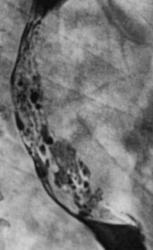

По представленным снимкам, у меня сложилось впечатление что пищевод как бы сдавлен извне (овал), возможно образованием в заднем средостении; при этом на довольно продолжительном участке есть нарушение архитектоники складок слизистой с множественными участками barium depletion (стрелки), свидетельствующими в пользу изъязвления.

А по поводу представленного случая, мне кажется слизистая прослеживается на всём протяжении, местами депо-бария, однако ближе к ретрокардиальному сегменту некоторые сомнения есть. На первом месте думаю что лейомиома( часто главным осложнением является кровотечение), а 2ом образование средостения.

Коллега v1tal: "А по поводу представленного случая, мне кажется слизистая прослеживается на всём протяжении, местами депо-бария, однако ближе к ретрокардиальному сегменту некоторые сомнения есть. На первом месте думаю что лейомиома (часто главным осложнением является кровотечение), а 2 ом образование средостения".

На серьи некоторых снимков у меня складывается впечатлене о наличие магкотканного компонента данного образования, может это и иллюзия, но хочу подвести к тому что при злокачестенном образовании данной протяженности( а тут более 10см), были бы клинические проявления как общего состояния пациента так и со стороны анализов крови. Так что надо думать о наличие доброкачественного образования, другое дело что эндоскописты не могут подлезти к этому "делу" ни как это возможно при не измененной слизистой. Надо настаивать на взятие повторного биоптата.

Исходя из вышесказанного, по данному случаю: сдавление просвета и смещение пищевода мягкотканным образованием, выходяшим за пределы стенки, изъязвление передней стенки пищевода. Заключение: подслизистая опухоль пищевода с изъязвлением, вероятнее всего лейомиома. Рекомендации: эндоУЗИ с биопсией, КТ.